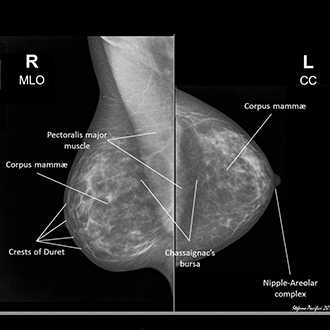

Mammography is important because in its earliest stages breast cancer may not be palpable; it may be too small to feel as a lump or tissue change. Mammography can help detect these changes two years or more before you would feel them. Physical examination is also important because premenopausal breast tissue is often dense and fibrous, which may decrease the reliability of mammography for young women.

Breast screening (mammography) is an X-ray examination of the breasts Breast screening can show breast cancer at an early stage, when they are too small for you or your doctor to see or feel

Some women find the procedure uncomfortable and few may find it painful. We need to press to produce good quality mammograms at a low radiation dose. The pressure will only last for a few seconds. If you do experience pain, it usually only lasts for long as the procedure takes.